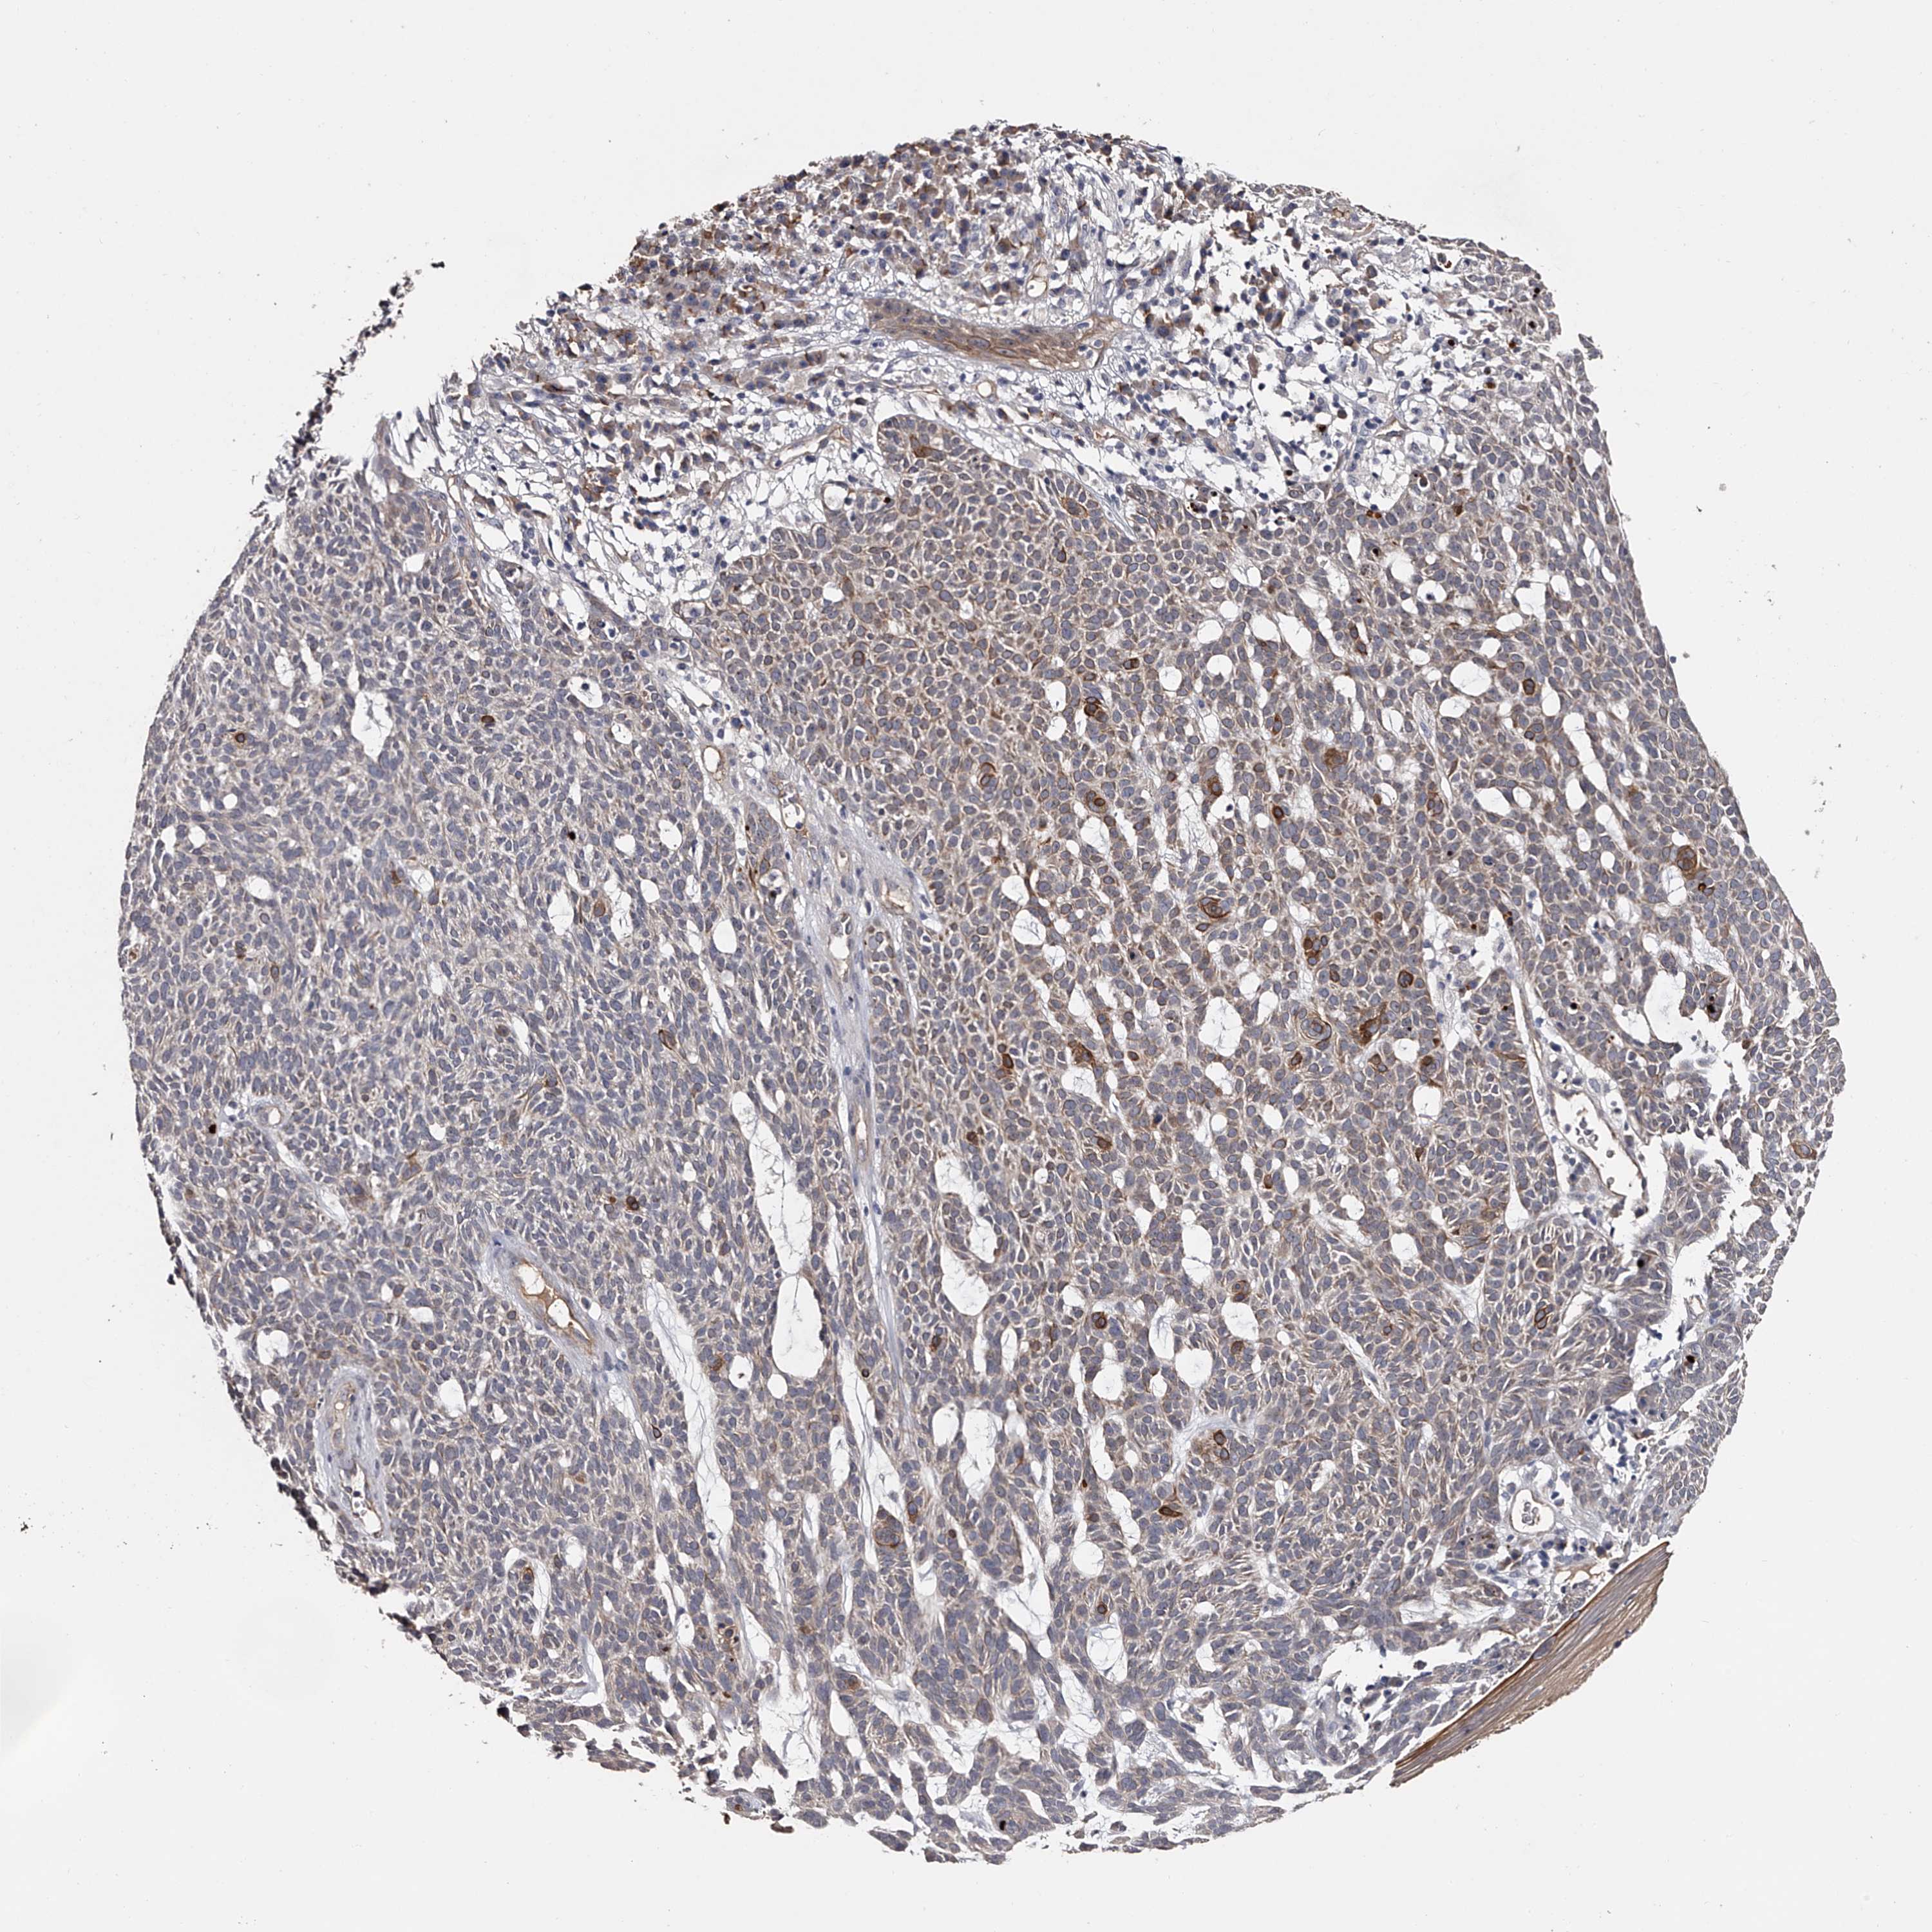

SKIN CANCER - Protein expressioni

A mouse-over function shows sample information and annotation data. Click on an image to view it in a full screen mode. Samples can be filtered based on level of antibody staining by selecting one or several of the following categories: high, medium, low and not detected. The assay and annotation is described here.

Each image is clickable and will lead to virtual microscopy that enables deeper exploration of all samples and also displays staining intensity scores, fraction scores and subcellular localization as well as patient and tissue information for each sample.

Antibody HPA029666

Antibody HPA029667

Antibody HPA029668

Antibody HPA029669

Basal cell carcinoma

Squamous cell carcinoma, NOS

Squamous cell carcinoma, metastatic, NOS